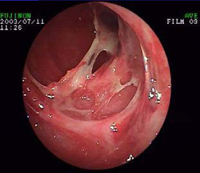

坏死性小肠炎的典型病理变化为坏死性炎症改变。自粘膜下层开始,随病变的扩大,可向肌层及粘膜层发展,使多处肠壁全层充血水肿甚至溃疡穿孔引起腹膜炎。病变多见于空肠下段和回肠上段,严重才全部小肠均可受累。一般呈散在性、节段性排列,有的为1~2段或2段以上,每段长短不一,最短10余cm,长者可达100cm,分界清楚。受损肠壁增厚,质脆失去弹性、扩张。重者浆膜面粗糙有纤维素附着,肠腔内充满果酱样血便。显微镜下可见病变肠壁各层均有炎症细胞浸润,以淋巴细胞、嗜酸性白细胞、单核细胞、浆细胞为主。粘膜可发生坏死或脱落,粘膜下层有大片出血坏死和水肿,毛细血管扩张充血。腹腔内可有混浊、脓性或血性渗液。病变恢复后不遗留慢性肉芽肿性改变,引起腹腔内粘连者少见。

一般无前驱症状、起病急聚。主要表现腹胀、腹痛、呕吐、腹泻、血便、发热,不少患儿在1~2日内出现严重中毒症状,甚至休克。腹痛为持续性,伴阵发性加剧。常为全腹痛,也可局限于病变部位。发病后不久即出现呕吐、腹泻。大便初为水样,含粘液、后即变为血便。部分病儿无腹泻,腹痛1~2日后即开始便血。便血量不等,大量便血者均为暗红色,伴有腐败腥臭味,呈洗肉水或红果酱样。有些患儿于发病数小时后即出现血便。发热在38℃左右,中毒严重者体温可高达39~49℃以上或低于正常。婴幼儿症状多不典型,脱水酸中毒症状明显,有些可出现肠道外症状,如黄疸、咳喘、肝脾大及惊厥等。